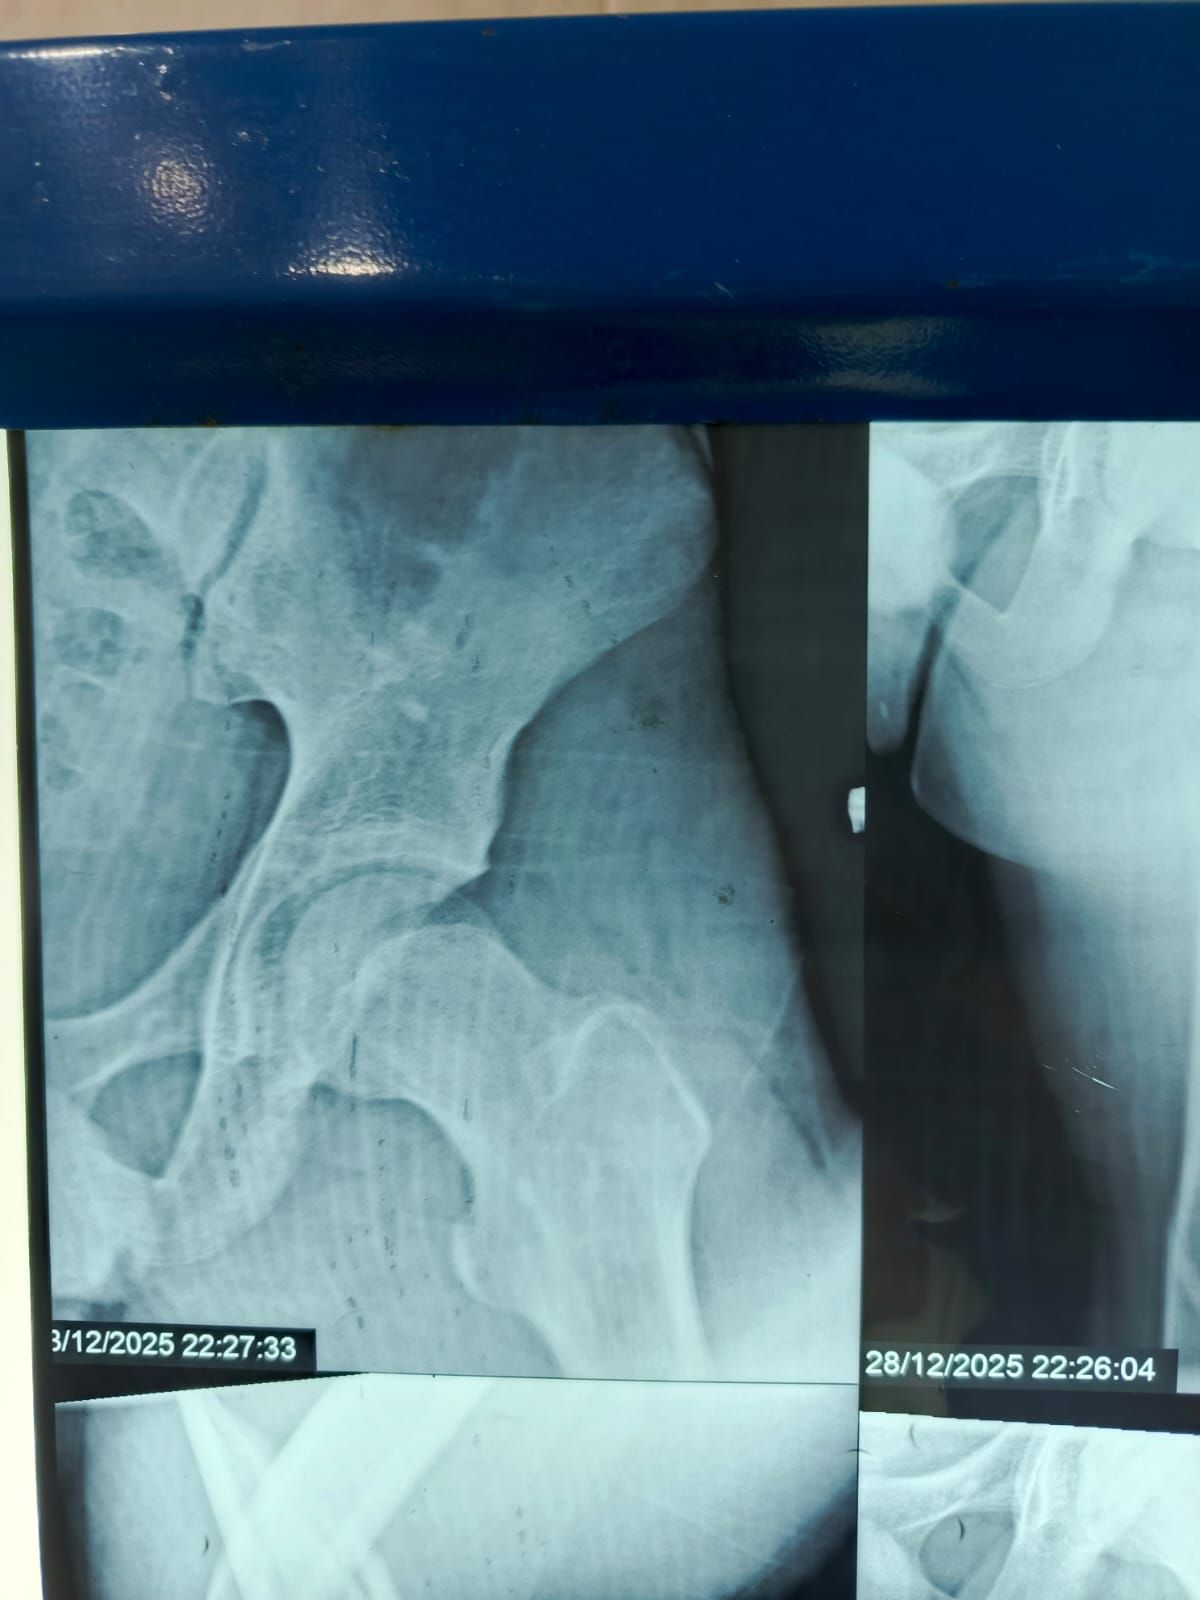

نجح الفريق الطبي بقسم الطوارئ والعمليات بمستشفى مغاغة العام بمحافظة المنيا ، في إنقاذ شاب يبلغ من العمر 16 عامًا، تعرض لحادث مروري مروع أسفر عن كسر مفتت متعدد المواضع بعظمة الفخذ الأيسر، وذلك من خلال إجراء جراحة متقدمة باستخدام تقنية المسمار النخاعي التشابكي في زمن قياسي.

وفور وصول المصاب إلى قسم الطوارئ، جرى التعامل الفوري معه، وتم اتخاذ القرار الطبي العاجل بإجراء جراحة المسمار النخاعي التشابكي دون فتح موضع الكسر، بما يتوافق مع أحدث البروتوكولات الطبية العالمية. واستغرقت العملية نحو ساعتين ونصف فقط، غادر بعدها المريض غرفة العمليات في حالة مستقرة.